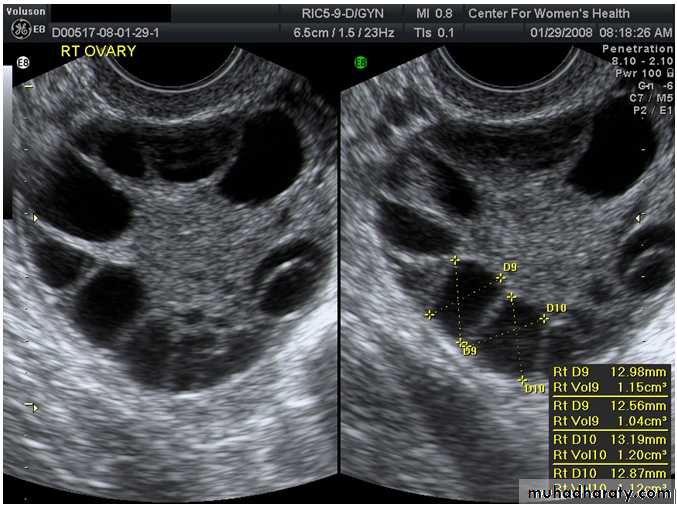

What is the name of the procedure? For what it is used?If the result is abnormal what is the next investigation?

What is this abnormality/